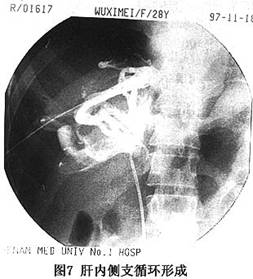

正常肝靜脈造影應爲棒狀或伴有部分分支顯影,造影劑經下腔靜脈流入右心房。當肝靜脈出口部受阻時,可見主肝靜脈及其引流區域的肝靜脈支增粗(圖6)。慢性病例,可見肝內形成側支循環,出現“蛛網徵”(cobweb’sign,圖7),如若下腔靜脈病變隔膜位於主肝靜脈出口部以上,且肝靜脈本身未被累及時,可見主肝靜脈擴張,下腔靜脈亦擴張(圖4)。在急性病例,肝靜脈可有狹窄、階段性阻塞,在肝內可見側支循環形成或與門靜脈分支形成短路,此時門靜脈干支亦可顯影。少數急性或亞急性病例,除肝靜脈廣泛狹窄外,其出口部阻塞或呈沙漏狀,此與肝小靜脈阻塞病(venoocclusive disease of the liver,VOD)相當難以鑑別。當主幹靜脈完全受阻時,造影劑經肝內的側支循環,再由肝短或肝背靜脈在第三肝門部流入下腔靜脈,這些靜脈數目不一,有時很粗大,特別是肝右後下靜脈,直徑有時可達2.0cm(圖8)。值得強調指出的是不少B-CS病例(如Ⅱ型和Ⅲb型),主肝靜脈出口部閉塞,經下腔靜脈插管做逆行肝靜脈造影,是難以實施的,對這種病例,經皮肝穿肝靜脈造影對B-CS的診斷,更有決定性的意義。